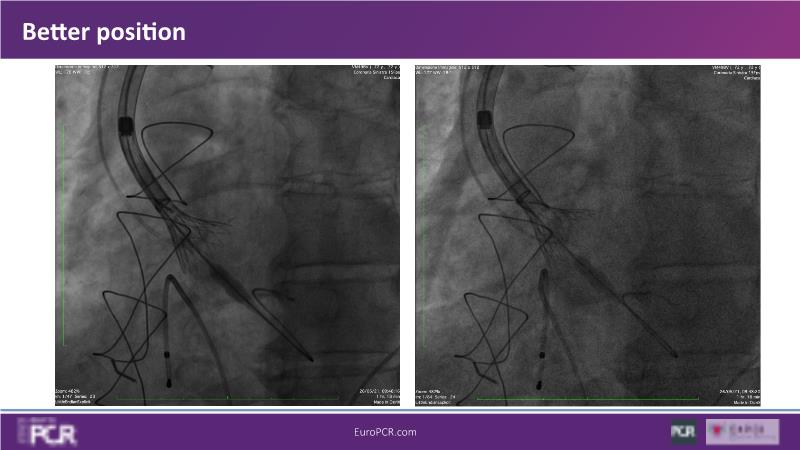

Discover the key factors to consider in selecting the optimal valve and implant technique for transcatheter aortic valve implantation (TAVI) to achieve optimal procedural outcomes. Gain insights into the impact of device choice and implantation technique on coronary access following TAVI and learn valuable strategies for tailoring your TAVI technique to complex scenarios, including bicuspid aortic valves, large and calcified anatomies, and ensuring coronary access.

- To learn what to consider when determining valve selection for TAVI

- To learn how to tailor your TAVI technique to complex situations: bicuspid aortic valves, large, calcified anatomies and coronary access